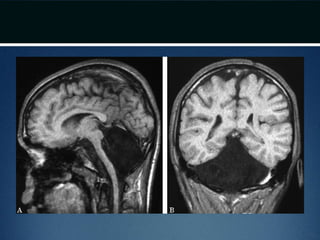

Chiari II malformation •Caudal displacement of cerebellar vermis, lower brainstem and fourth ventricle seen exclusively in patients with myelomeningocele • Numerous other anomalies associated in various combinations – vertical straight sinus – large venous lakes in the tentorium – fenestrations in falx, which is often not well formed – gyri of left and right hemispheres interdigitate – “Chinese lettering” on axial MRI